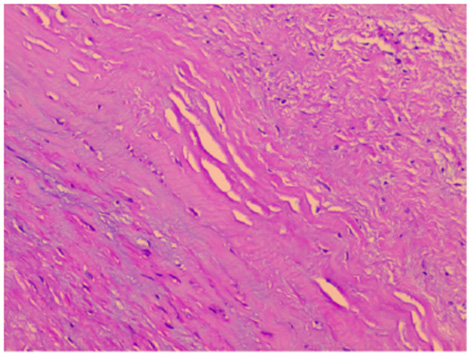

Figure 4

Histological examination. Histological examination revealed massive fibrous tissue in the aneurysm wall (Figure ×200).

During surgery, after sternotomy and the pericardium being incised, we found that the aneurysmal portion of the left ventricle was thinned and was greatly expanded (Figure 2A), and there was no pericardial adhesion. The myocardial layers were continuous, the aneurysm well had sharply defined edges (Figure 2A). After being surgically incised, the bovine pericardium was used to close the aneurysm's neck (Figures 2B,C). Felt pads were then employed to close the epicardium over the patch (Figure 2D), resulting in a detour formed around the posterior descending artery (Figures 2E,F). The third strip of the felt pad reinforced the “sandwich” structure (Figure 2F). A right atriotomy was performed to repair the anterior leaflet of the tricuspid valves with a 5 mm tear. 5.0 Prolene suture lines were utilized to sew the rupture, and valvuloplasty of the anterior tricuspid leaflet was performed (Figures 2G–I). 5.0 Prolene suture was used to figure-of-eight suture on the junction between the anterior annulus and the posterior annulus, and the junction between posterior annulus and septum annulus. Testing with saline solution injection and intraoperative esophageal echocardiography showed no tricuspid regurgitation (Figures 2I, 3A) and revealed no residual shunt for LVPW (Figure 3B). Histological examination demonstrated massive fibrous tissue in the aneurysm wall,myocardial fiber disappears is replaced by hyperplained fibrous tissue, fibrous connective tissue increases, and glass -like changes in local fiber tissue (uniform consistency, no structure and translucent protein accumulation) (Figure 4, ×200), consistent with trauma-induced aneurysms. The sketch of ventricular aneurysmorrhaphy and tricuspid valvuloplasty was provided (Supplementary Figures S1, S2). The postoperative CT scan and reconstruction revealed successful surgery (Figures 3C,D). One week after surgery, the patient was discharged, and follow-up care was provided in the outpatient setting. Finally, the child recovered well and was followed up for 12 months.